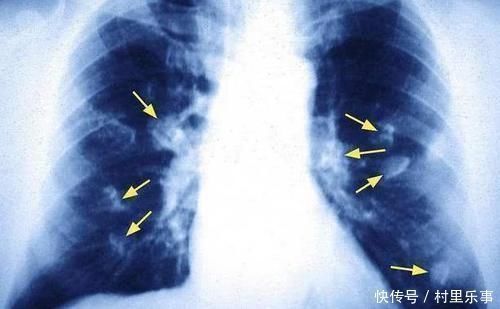

文章插图

■身体出现这4个表现,可能肺癌早期的信号,还请及时就诊检查!

●经常咳嗽不断:

日常生活中,肺癌早期的一个主要表现就是不断咳嗽,并且表现为干咳,又或是没有痰液,又或是咳出来的痰液是白色泡沫痰。而这些情况,都是由于长期吸烟而引起的,所以很多朋友都对这个问题忽视了。

●出现咯血问题:

日常生活中,倘若你的体内出现了肿瘤,那么势必就会直接损伤我们的支气管血管,这个时候就很容易导致咳出来的痰液中会带有血液,可能这个时候是痰液带有血点,又或是痰液中带有血丝。通常来说,患有早期肺癌的患者,很多时候都会出现咯血情况,所以平时大家也需要多加留意。

●胸部出现疼痛:

日常生活中,倘若肿瘤的位置比较靠近我们身体的胸膜位置,那么就很容易会导致身体出现隐隐疼痛的情况,甚至有时候还会直接影响到我们的呼吸,甚至还可能会让咳嗽症状变得更加严重。通常来说,这种情况下也需要警惕肺癌风险。

●其他症状表现:

日常生活中,在肺癌早期阶段,患者还会出现胸闷气短、发热等问题。但是肺癌早期这些情况还是很少会出现,通常都会在经过一系列的相关检查之后才能够察觉出来。